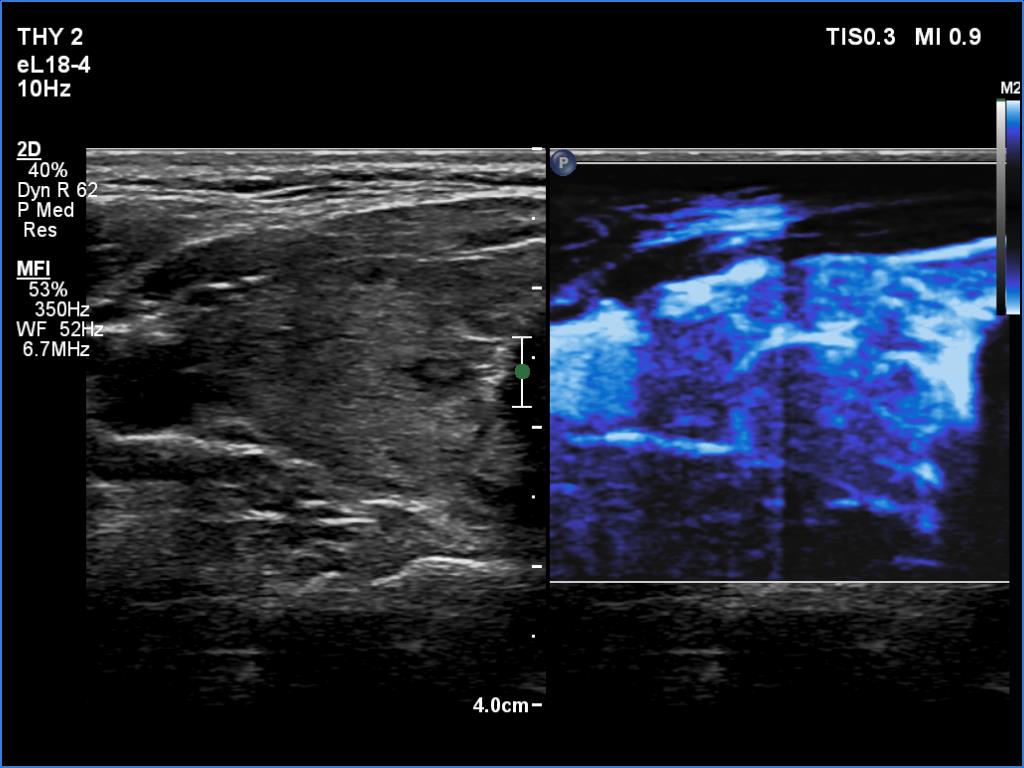

Right lobe, color Doppler mode

Right lobe, microflow imaging